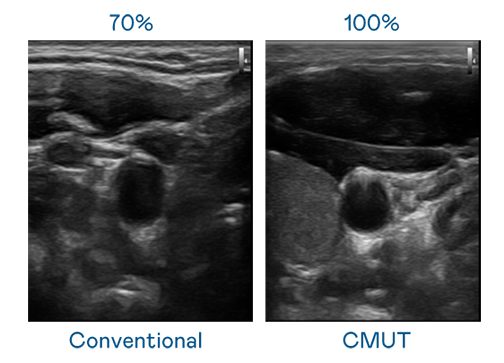

CMUT 技术是一种用电容式微机电元件来产生超音波讯号的技术。与传统 PZT 压电式技术相比,CMUT 频宽增加 30%,更宽频的超音波讯号让影像解析度大幅提升,是实现高影像品质医疗超音波扫描、促进精准医疗发展的关键技术。

超音波影像的解析度高低,首先取决于探头能发出的讯号频宽。918博天娱乐 CMUT 可提供高清晰的超音波讯号,提供高频宽、高灵敏度、影像纹理细节更高的超音波影像,协助医护人员缩短影像判读时间及利用精准的医疗影像进行诊断。